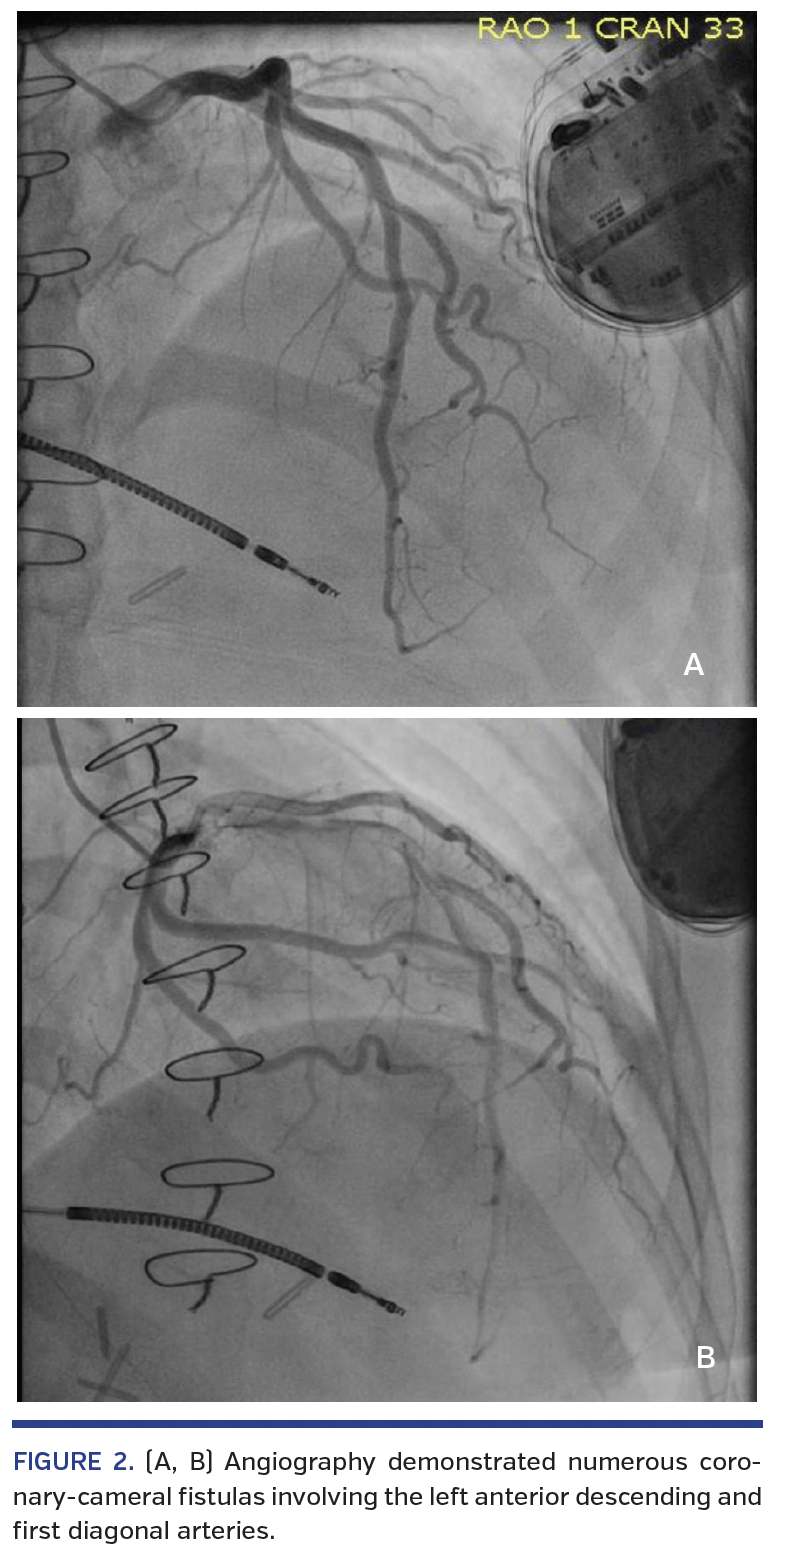

The patient is a 44-year-old woman with a history of HCM. She presented to our cardiovascular center 1 month after undergoing septal myomectomy for HCM along with repair of an apical aneurysm with thrombus evacuation; her surgery had been deemed a success, with reduction in left ventricular septal size from 30 mm to 8 mm and complete elimination of obstructive gradient. In the month after her surgery, she developed progressive exertional dyspnea, dependent edema, and orthopnea. She was admitted and a repeat echocardiogram demonstrated a reduction in left ventricular ejection fraction to 25% from a previous 60%, along with a diastolic flow signal emanating from the ventricular septum (Figure 1). The patient subsequently underwent coronary angiography. This demonstrated numerous CCFs involving the left anterior descending and first diagonal arteries (Figure 2), as well as the right posterior descending artery (Figure 3). No significant coronary artery disease was noted. No intervention was performed. The patient was subsequently started on neurohormonal blockade for newly diagnosed heart failure and discharged with referral to the Advanced Heart Failure service for continued care.